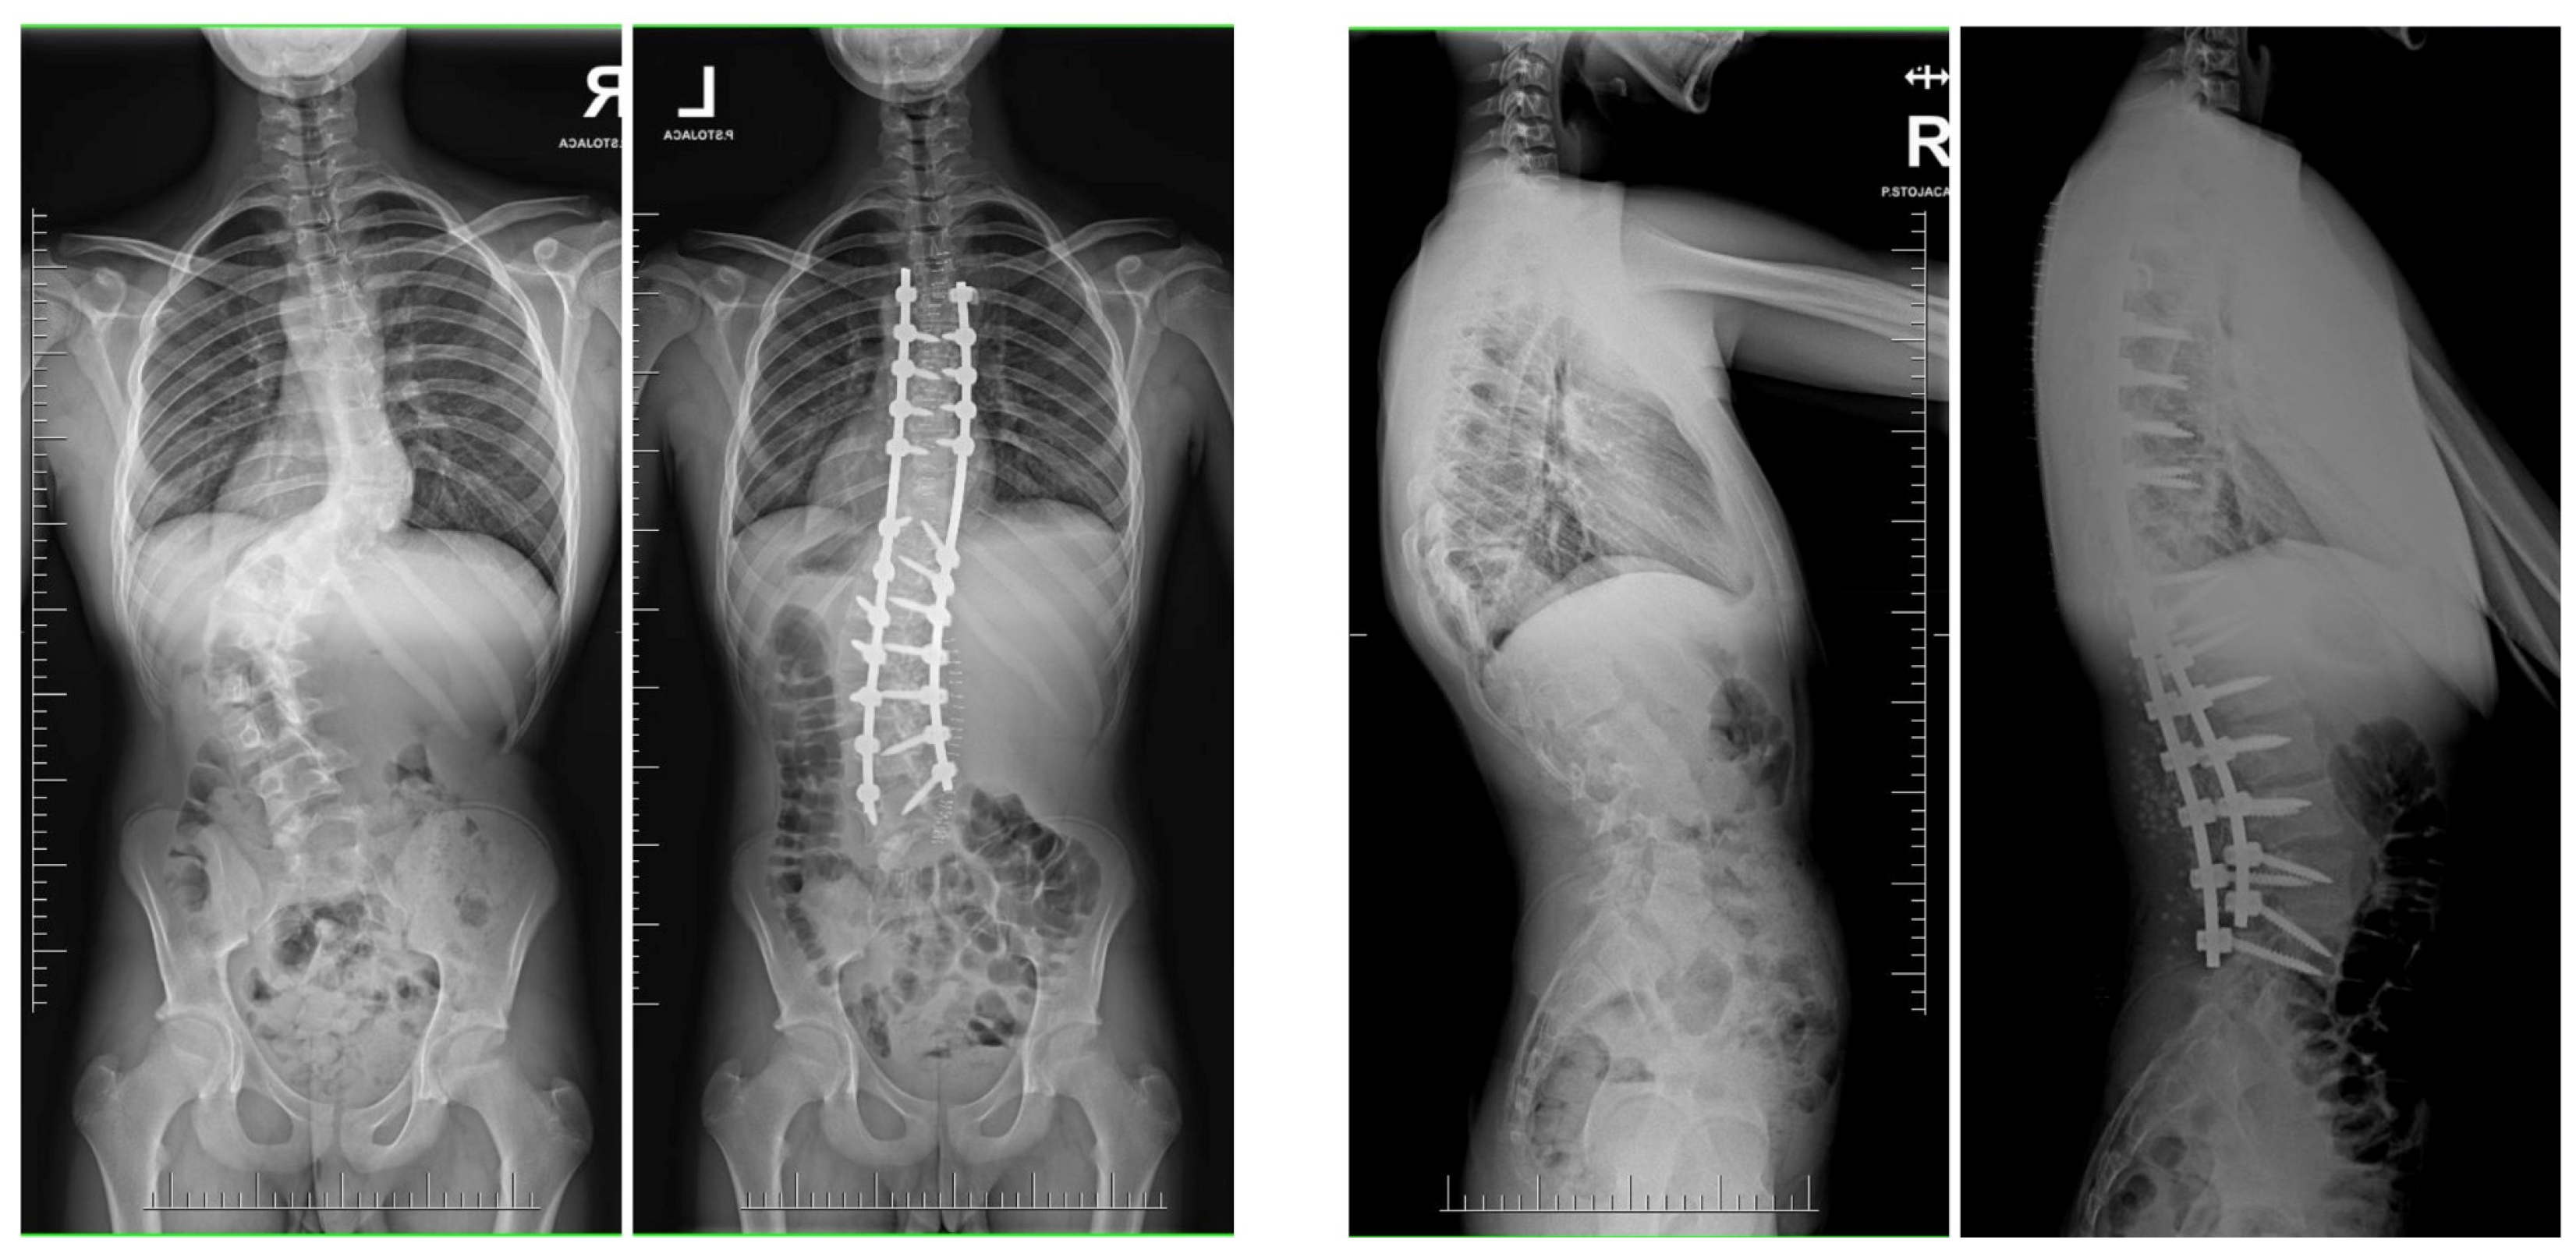

Surgical Treatment Strategies for Severe and Neglected Spinal Deformities in Children and Adolescents without the Use of Radical Three-Column Osteotomies

10. Rib Resection/Thoracoplasty